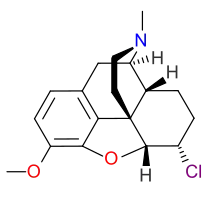

Morphides

- α-Chlorocodide (= chlorocodide)

- β-Chlorocodide

- α-Chloromorphide (= chloromorphide)

- Bromocodide

- Bromomorphide

- Chlorodihydrocodide

- Chloromorphide

- Codide

Structures

| Morphides | ||||

|---|---|---|---|---|

α-chlorocodide α-chlorocodide |

β-chlorocodide β-chlorocodide |

Bromomorphide Bromomorphide | ||

Chlorodihydrocodide. Chlorodihydrocodide. |

Chloromorphide Chloromorphide |

Codide Codide | ||